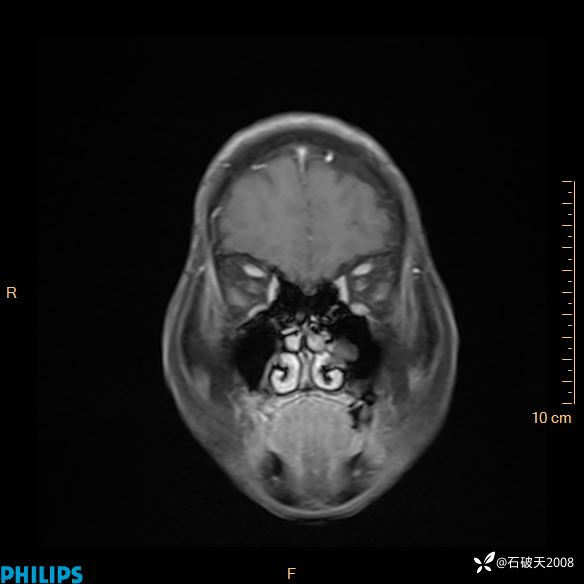

2024.2.21MR

增强轴位